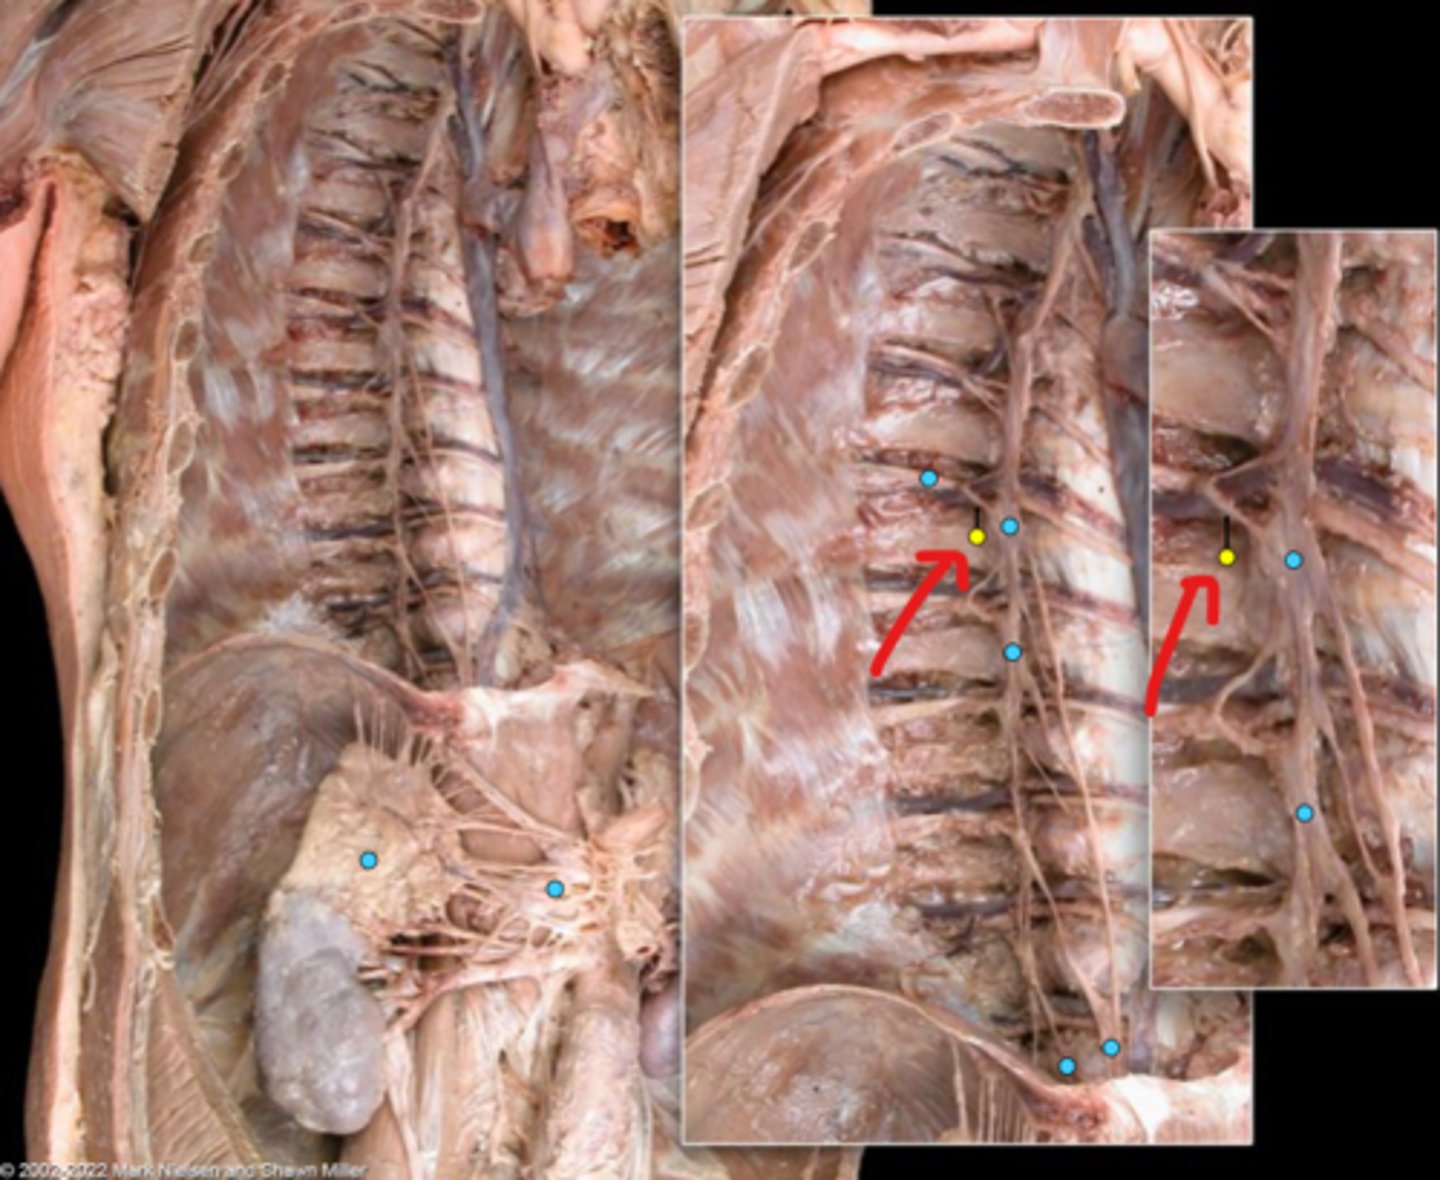

Suprarenal gland

Celiac ganglion

Intercostal nerve

Communicating ramus

Sympathetic trunk ganglion

Sympathetic trunk

Lesser splanchnic nerves

Greater splanchnic nerve

Anterior (ventral) ramus

Spinal nerve trunk

Posterior (dorsal) ramus

Spinal ganglion